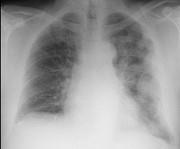

52岁,男,胸痛、体重下降,请结合胸片选出最可能的诊断 ( )A.包裹性胸腔积液B.胸膜肥厚C.化脓性胸膜炎D.肺癌E.胸膜间皮瘤

问题 52岁,男,胸痛、体重下降,请结合胸片选出最可能的诊断 ( )

选项 A.包裹性胸腔积液 B.胸膜肥厚 C.化脓性胸膜炎 D.肺癌 E.胸膜间皮瘤

答案 E